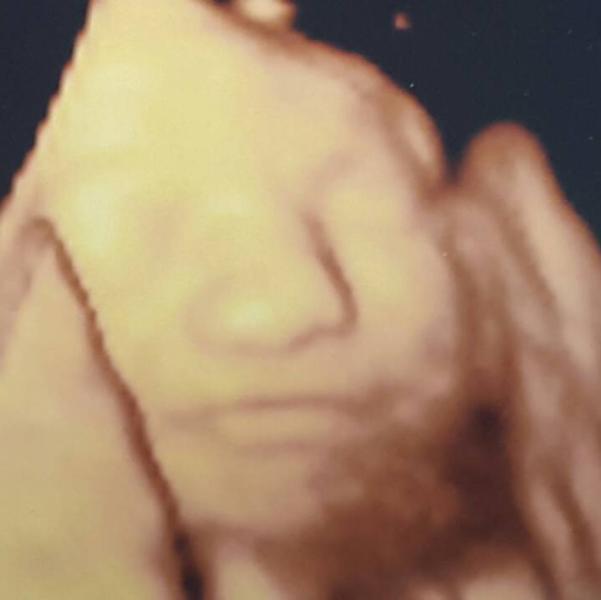

my smiling baby girl :)